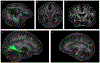

Methods: Twenty-four patients with MDD (11 women) and 24 age-matched healthy control participants (7 women) underwent diffusion-weighted imaging with a 1.05-mm isotropic resolution at 7T. Amygdala nuclei regions of interest were obtained through automated segmentation of 0.69-mm resolution T1-weighted images and 0.35-mm resolution T2-weighted images. Probabilistic tractography was performed on all subjects, with random seeding at each amygdala nucleus.

Results: The right lateral, basal, central, and centrocortical amygdala nuclei exhibited significantly increased connection density to the rest of the brain, whereas the left medial nucleus demonstrated significantly lower connection density (false discovery rate p < .05). Increased connection density in the right lateral and basal nuclei was driven by the stria terminalis, and the significant difference in the right central nucleus was driven by the uncinate fasciculus. Decreased connection density at the left medial nucleus did not appear to be driven by any individual white matter tract.

Conclusions: By exploiting ultra-high-resolution magnetic resonance imaging, structural hyperconnectivity was demonstrated involving the amygdaloid nuclei in the right hemisphere in MDD. To a lesser extent, impairment of subnuclei connectivity was shown in the left hemisphere.